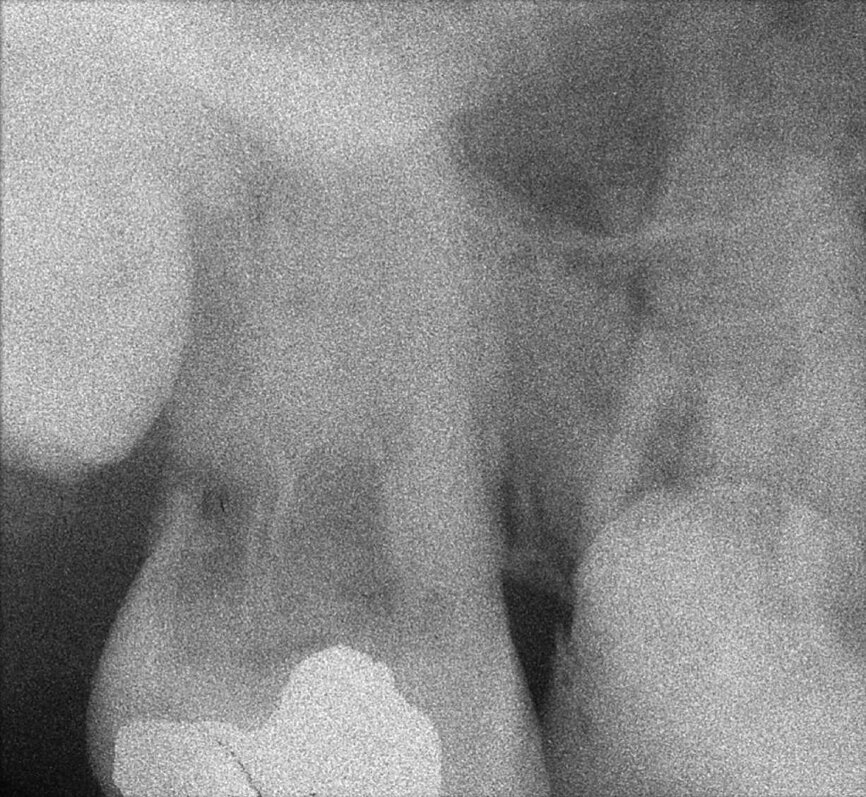

Le cas avec lequel je souhaite commencer mon exposé clinique est un exemple parfait de la difficulté à définir l’origine des symptômes d’un patient, par l’examen d’une simple radiographie intraorale. Non seulement l’examen 2D ne permet pas d’établir avec certitude la présence d’une lésion, mais surtout, il est impossible d’en déterminer la taille, la morphologie et le type. Au contraire, une analyse de l’imagerie 3D offre une image claire de la situation clinique. Chez ce patient, les coupes coronales et sagittales révèlent la présence d’une importante lésion s’étendant de l’apex de la racine mésiale de cette molaire jusqu’à la zone de furcation, tandis que les coupes axiales nous permettent d’analyser précisément l’anatomie endodontique et, en particulier, la forme de la racine mésiale, qui apparaît fusionnée avec la racine palatine. Un panorama complet du cas peut donc guider le processus de décision et orienter le plan de traitement vers une modalité bien précise de traitement (Figs. 1–4).